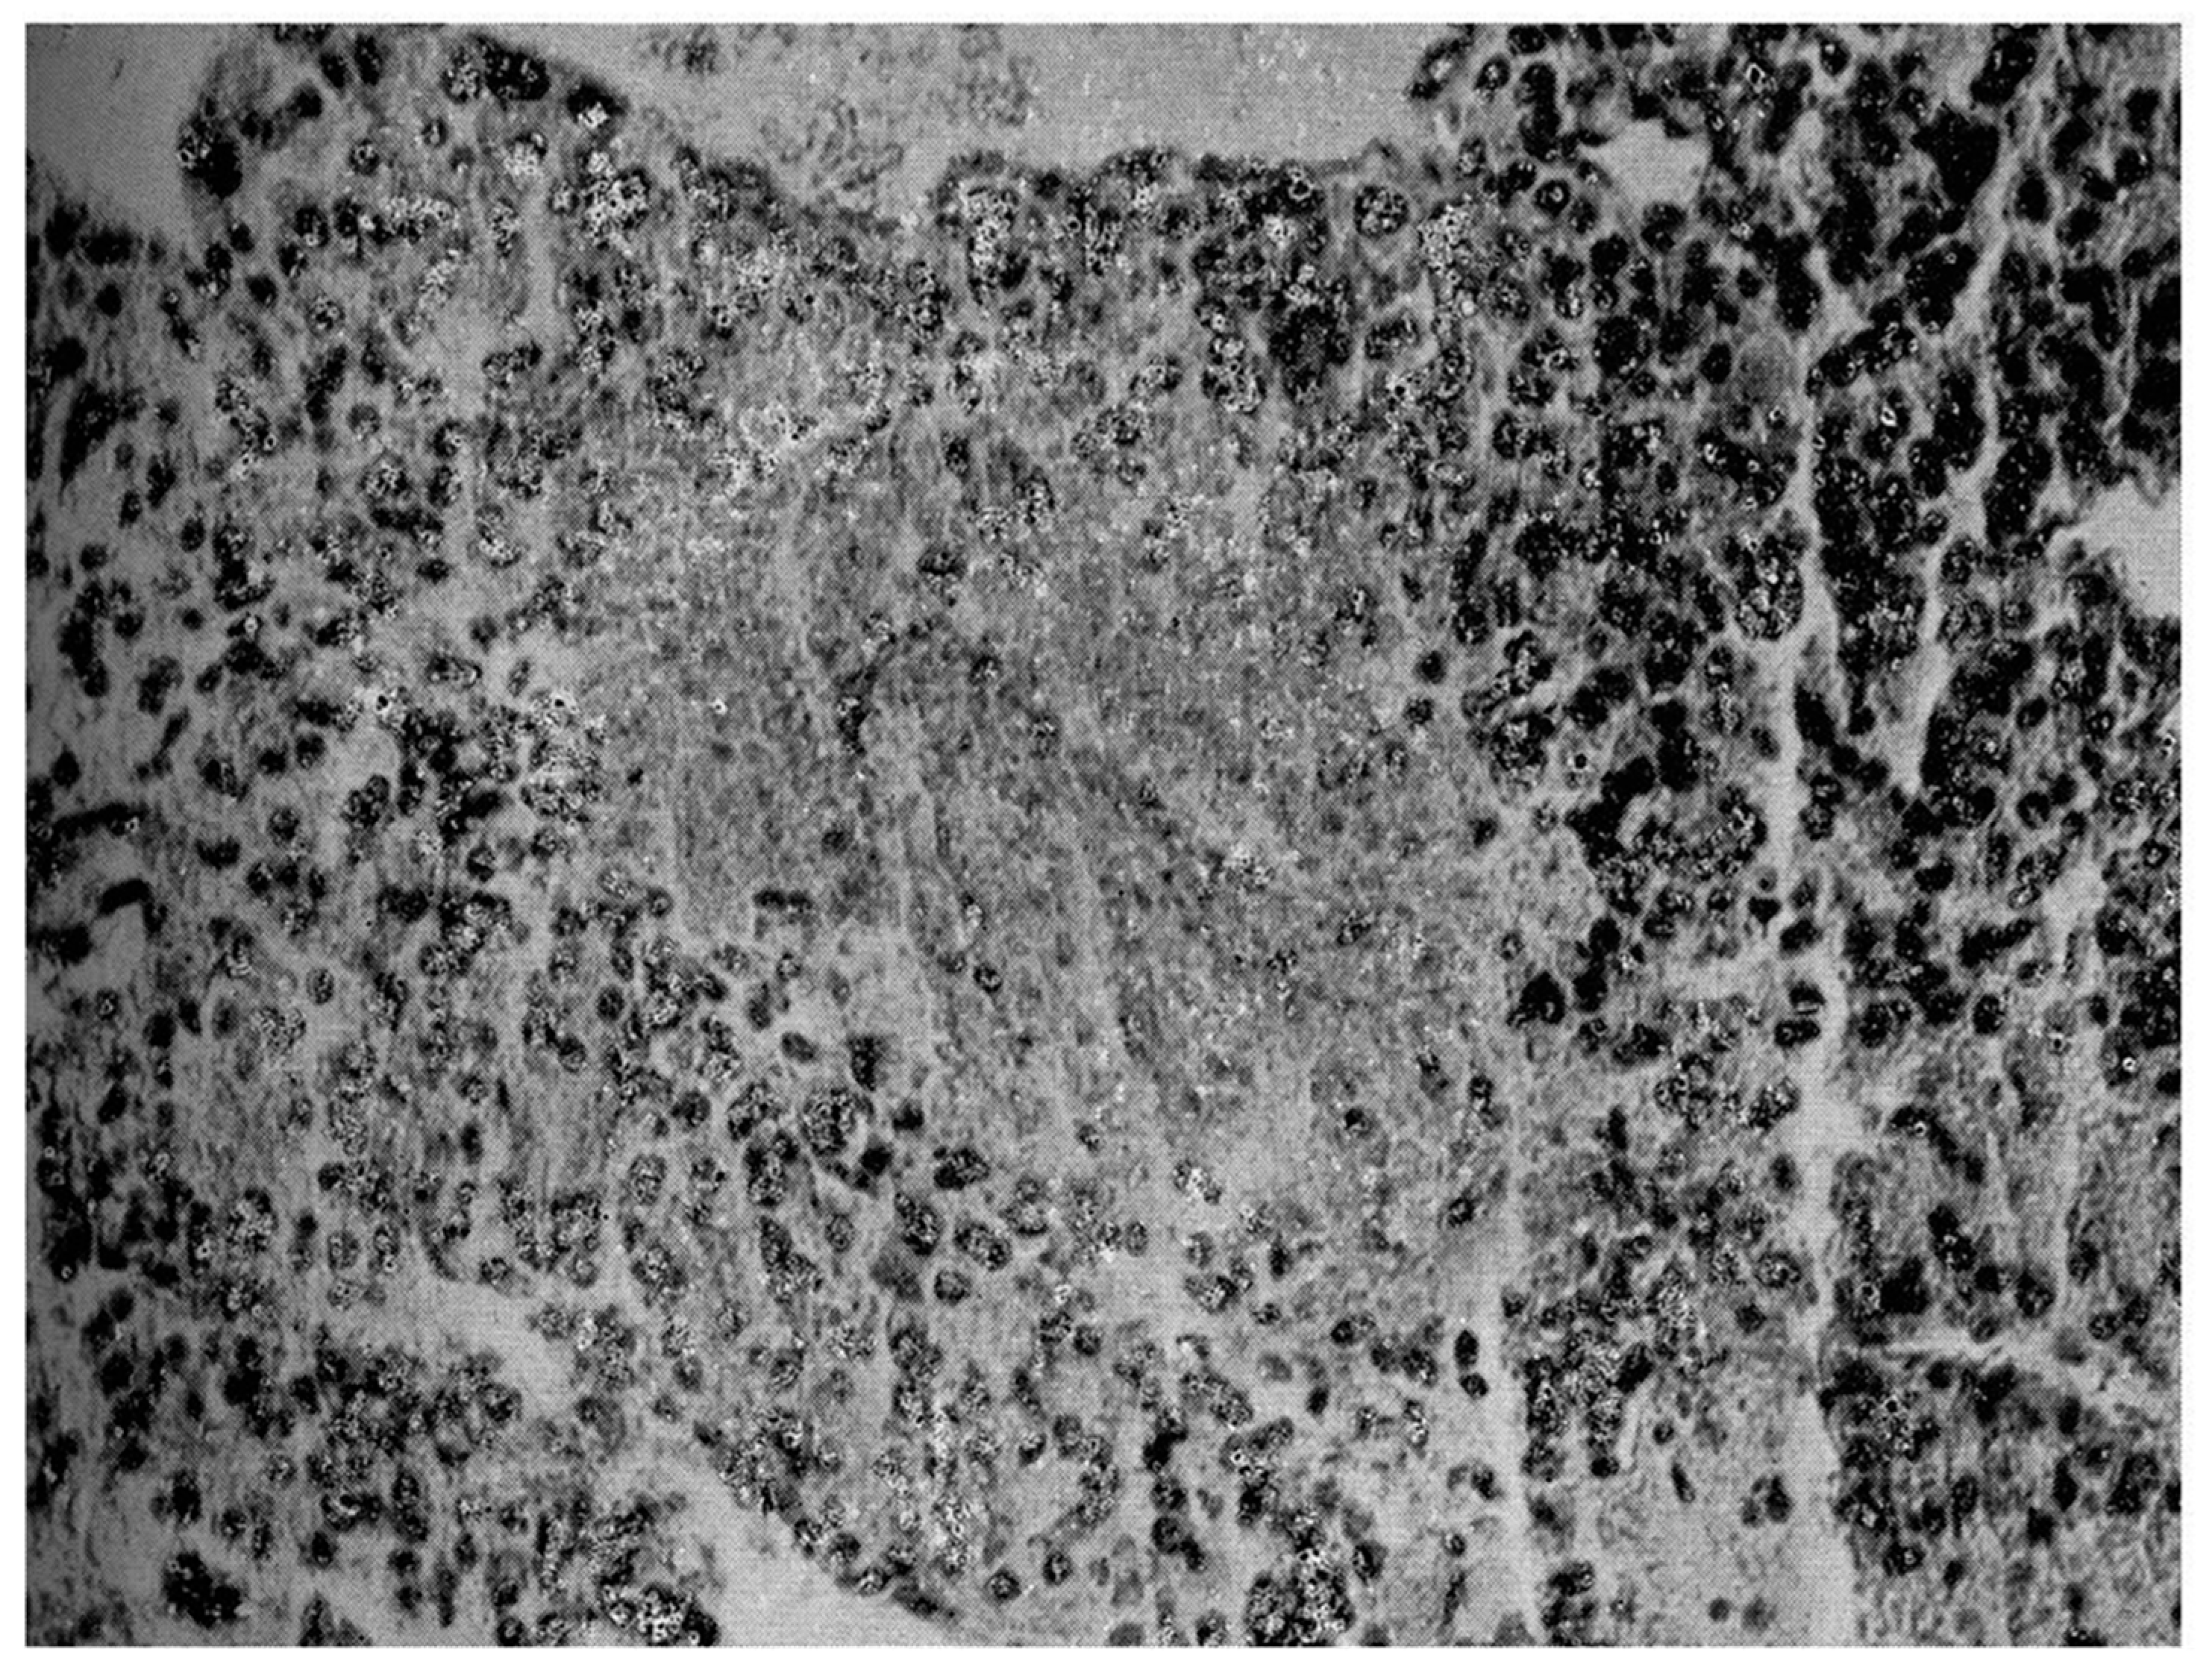

2. Case 1

3. Case 2